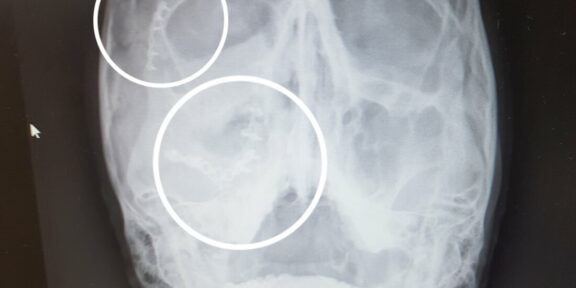

RTG s vyznačením titanu.

Dnes jsou to čtyři měsíce od zranění. Od té doby jsem se docela slušně rozlezl a rozjezdil na vodě. Pravou tvář mám zdobenou titanem tak, že podle rentgenu by mě vzali ke každejm správnejm punkáčům. Na lezci (server lezec.cz) je již někdo s přezdívkou Titanhead, tak já bych mohl bejt Titanface. Úlomky kostí utlačily jednu z větví trojklanného nervu a cit se do tváře stále ještě kompletně nevrátil. Tvář poctivě rehabilituji, ale stále je to boj s nejistým výsledkem, který se dostaví klidně až po roce. Musím smeknout poklonu mé paní doktorce operatérce, protože odvedla opravdu moc pěknou práci a už po pár dnech na mě nikdo nic nepoznal.